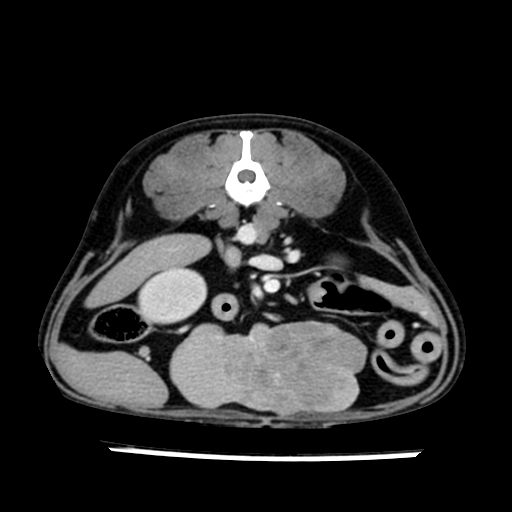

prescritto esame TAC

sequenza immagini limitata al fegato reni e surreni

le immagini ecografiche rispetto alla tac datano circa 7 mesi prima ,le surrenali sono normali nonostante il test acth sia risultato positivo .all’esame TAC dopo diversi mesi risultano aumentate armonicamente nel volume e si individua un forte sospetto di adenoma ipofisario .

sospetto adenoma ipofisario vs. meno probabilmente meningioma della base; intertiziopatia polmonare; lesione espansiva epatica, verosimilmente del lobo laterale sinistro, di sospetta natura neoplastica; lesioni spleniche di natura da definire; iperplasia/ipertrofia delle ghiandole surrenali, bilateralmente; vertebra di transizione del rachide toracico; tenosinovite cronica del muscolo bicipite brachiale di destra.

- la total body permette di escludere metastasi e di avvicinarsi all’interventistica

la tac dopo 7 mesi permette misure tridimensionali 5,2 x 9,2 x 4,5 cm (forma piu’ allungata )